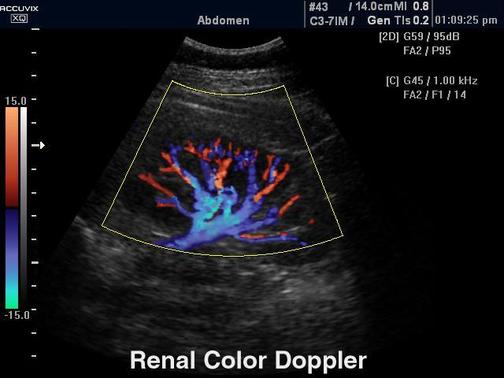

RENKLİ DOPPLER ULTRASONOGRAFİ

Renkli doppler ultrasonografi damar yapılarını değerlendirmek için kullanılan bir radyolojik tetkiktir. Bu inceleme ile damar yapılarındaki daralmalar, tıkanıklıklar, damar içerisinde pıhtı oluşumu, damarlardaki kan akım hızları saptanabilir.

Renkli doppler ultraonografi sıklıkla bacaklardaki varislerin, atardamar tıkanıklarının, boyundaki ana damarlarımızın (şah damarları) hastalıklarının, hipertansiyonu olan hastalarda böbrek damarlarındaki daralmaların, varikosel düşünülen hastalarda skrotal bölgedeki toplardamar genişlemelerinin tanısında kullanılır.